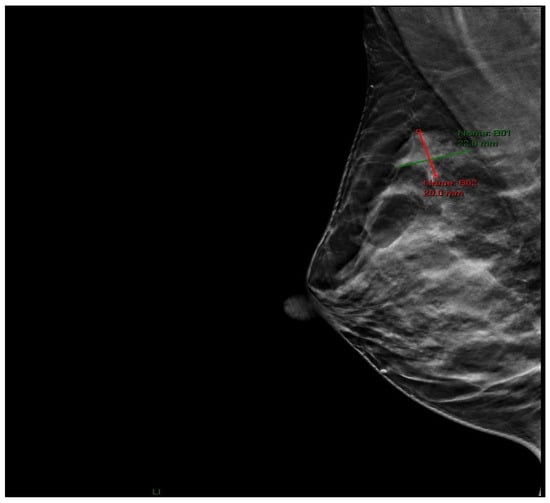

Physical examination revealed a palpable lesion in the right breast, cranially between 11 and 12 o’clock. Breast ultrasound showed a hypoechoic mass measuring 13 × 10 × 9.5 mm with irregular lobulated contours, a hypoechoic transition zone, and perifocal edema, without pathological axillary lymph nodes (BI-RADS 4). In June 2025, core needle biopsy confirmed invasive ductal carcinoma of the breast (HG 2, NG 2, ER 60%, PR 50%, HER2 3+, Ki-67 18%). Mammography confirmed a region of architectural distortion measuring 22 × 20 mm in the upper quadrants, prepectoral, 6 cm from the nipple, corresponding to the histologically verified tumor (BI-RADS 6) (Figure 1). The tumor was clinically staged as T1cN0M0.

Figure 1. Mammographic image (RMLO projection) showing an area of architectural distortion in the upper quadrants of the right breast.